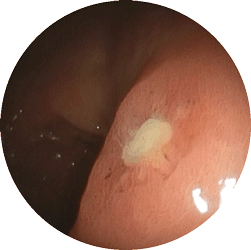

食道潰瘍内視鏡

食道潰瘍

心窩部の痛み、胸やけ、飲み込むときの胸の痛みで来院

内服薬1ヶ月で治癒